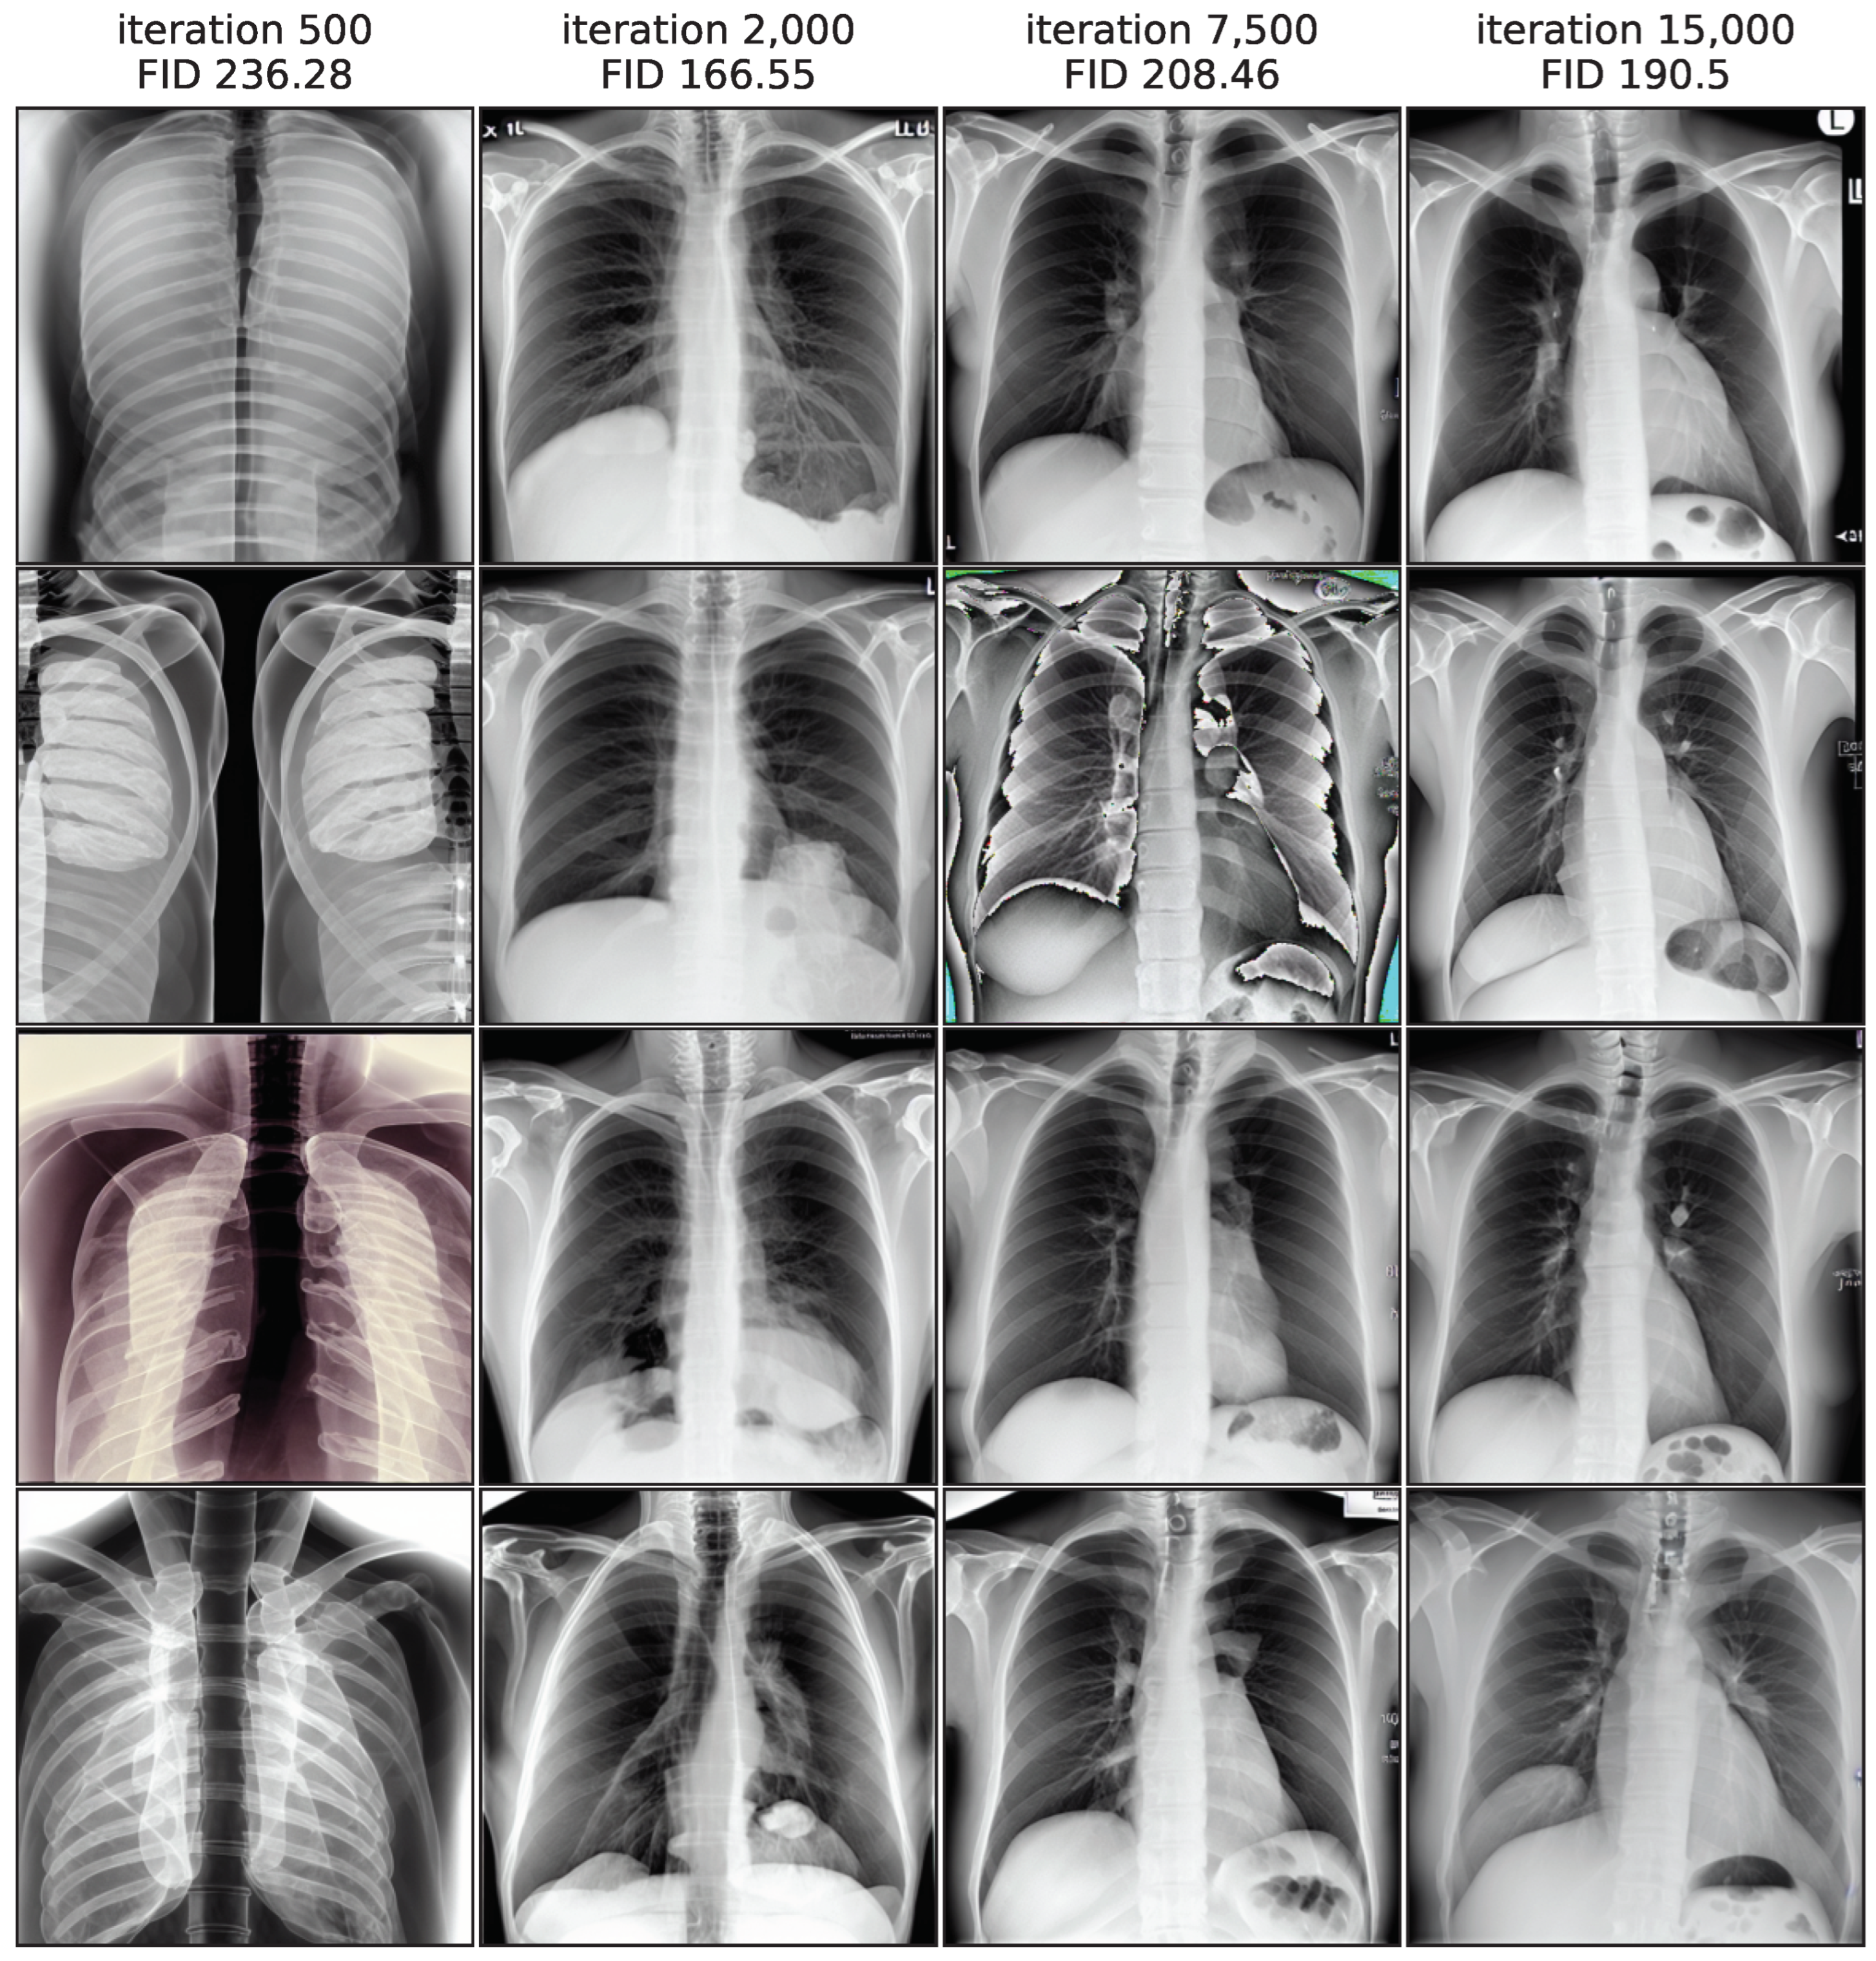

Figure 3 illustrates this by showing image samples of the LoRA model from different training iterations, while images from iteration 500 exhibit the largest FID values and a low quality, the quality improves substantially in iteration 2000. In iteration 7500 the FID rises again and the quality decreases, as shown clearly by a faulty image. In the end of the training process, the FID decreases again slightly and quality seems to increase, while not fully reaching earlier levels. This non-monotonic FID progression confirms the general usefulness of monitoring the FID values during the training process to pick the best model iteration.

Figure 3. Non-monotonic FID progression for LoRA model, showing 4 random samples per iteration.